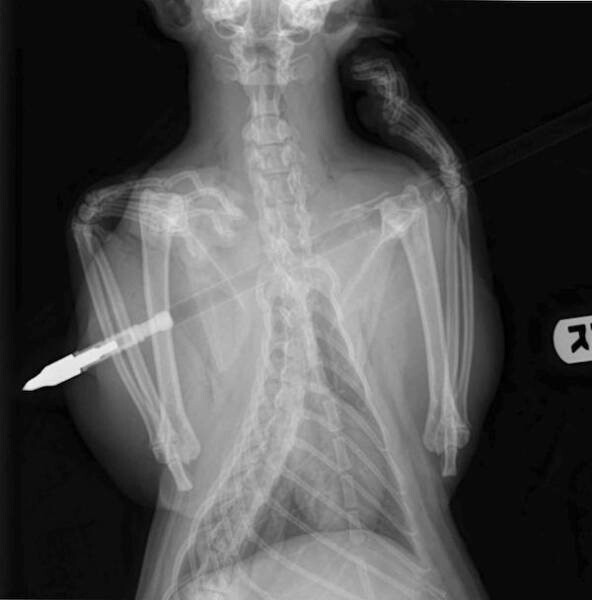

5. Стрела